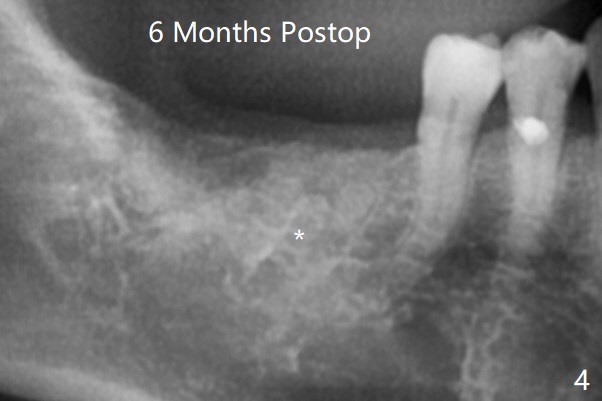

A 53-year-old man requests extraction of #30 and 31 post-SRP (Fig.1 (*: furca radiolucency). There is severe hemorrhage from the sockets post extraction, which makes bone graft difficult (Fig.2). Osteogen plug should have been used in stead of Ossogen. The socket openings are closed with 12x12 and 8x8 mm BioXclude and 4-0 PGA. The root curvature of the tooth #29 (Fig.2 *) suggests bruxism. The sockets heal 12 days postop (Fig.3). The septum at #30 (Fig.1 *) remains 6 months postop. Be wary of deviation off the septum during osteotomy. Bone density at #30 and 31 is high (1400-1700 units, Fig.5,6). Be careful of bone heat during osteotomy. It appears that cortical taps are pending.